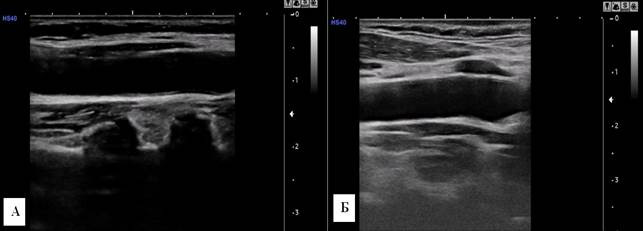

Аналогичные закономерности изменения количественных параметров артерий шеи в возрастном аспекте установлены и у женщин. Так, у женщин 20-35 лет размеры a. carotis communis dextra были равны: длина 68,9±1,7 мм, диаметр 6,3±0,1 мм, толщина комплекса интима-медиа 0,44±0,09 мм. А. carotis communis sinistra: длина 67,5±1,4 мм, диаметр 6,3±0,07 мм, толщина комплекса интима-медиа 0,45±0,10 мм (рис. 1).

Рис. 1. Сонограмма a. carotis communis dextra. А – мужчина, 30 лет; Б – женщина, 29 лет. У мужчины диаметр артерии больше.

Параметры комплекса интима-медиа без изменений